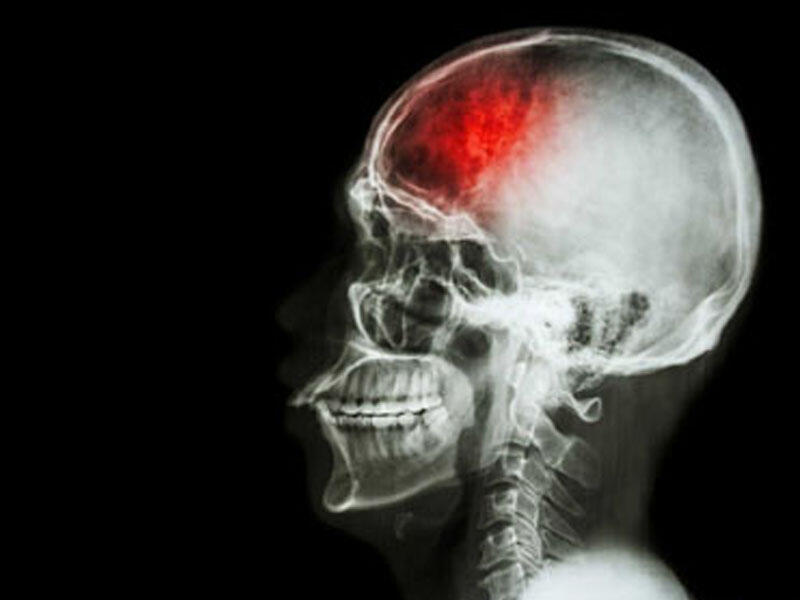

Kəllə beyin travmasının nəticələri

Beyin travması keçirmiş adamlarda bir-neçə ay ərzində diffuz baş ağrıları baş verə bilir.Bu ağrılar bəzən səhərlər baş versə də,çox vaxt gün ərzində gərginlik,narahatlıq törədir.Beyin travması almış xəstələrdə baş ağrıları aşağıdakı hallarda meydana çıxa bilir:

Beyin travması almış xəstələrdə bəzən zədə nahiyəsində lokallaşmış baş ağrıları meydana çıxır.Zədələnmə xəstələrdə ən çox baş gicəllənməsi,baş hərlənməsi,yeriş zamanı səndələmək,cəld hərəkətlər və yerdən qalxan zaman qətiyyətsizlik müşahidə olunur.Belə xəstələrdə bəzi beyin əlamətləri meydana çıxır:

Ağır kəllə beyin travması zamanı kəllə sinirlərinin zədələnməsi,hemiparez şəklində beyin pozulmaları müşahidə edilə bilir.Bəzən xəstələrdə hissiyyat və nitq pozulmalarına təsadüf edilir.

Şüurun pozulmasının dərinliyindən və ağırlığından asılı olaraq travmadan sonrakı ensefalopatiyanın baş vermə tezliyi artır.

Ensofalopatiya yaddaşın pozulmasına,şəxsiyyətin dəyişilməsinə,kəllədaxili təzyiqin pozulmasına səbəb olur.Ensofalopatiyanın klinikasının gedişi travmanın ağırlıq dərəcəsindən asılı olur.

Kəllə beyin travmalarının əlamətləri zədə dəydiyi andan 2 il və daha artıq bir zaman sonra meydana çıxa bilir.